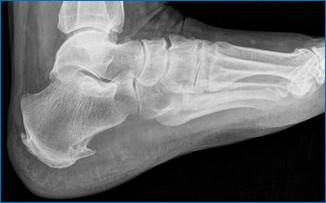

У пациентов пожилого возраста могут быть обнаружены пяточные шпоры как следствие инволютивных изменений в стопе. Это костные разрастания в виде шипа или клина в области энтезиса ахиллова сухожилия или подошвенной фасции. Подобные изменения могут быть визуализированы как рентгенологически (рис.10), так и эхографически (рис. 11).

Рис. 10. Пяточная шпора (рентгенологическая картина)